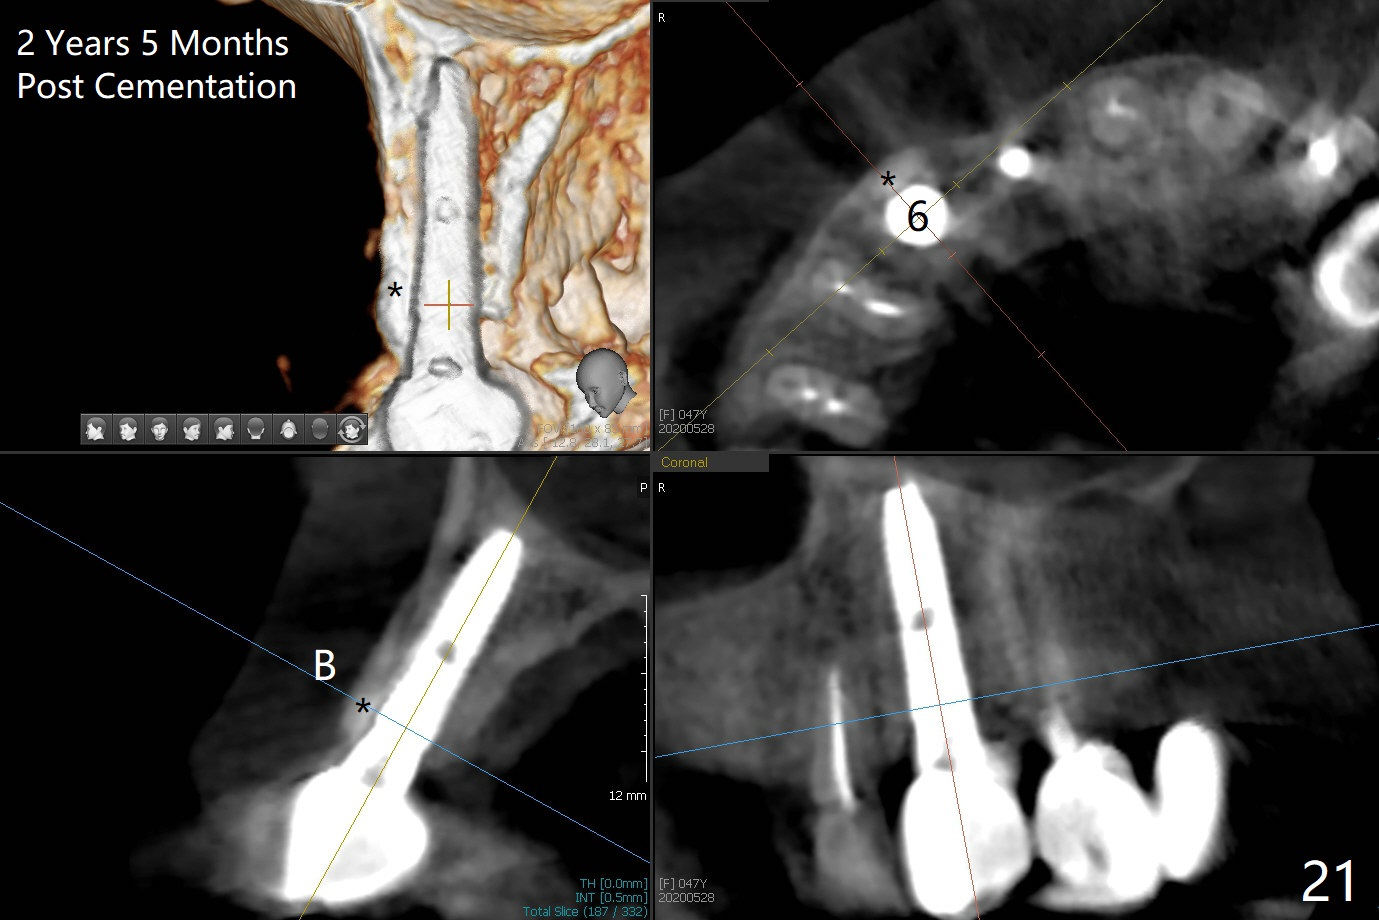

Since the ridge at #7 is ~ 4 mm, a 2.5x14 mm 1-piece implant is placed (Fig.8) after 1.2 mm (Fig.7), and 1.5 mm drills at 12 mm and 2 mm drill at 8 mm.  Later the implant is placed deeper (Fig.10).  There is no bone loss 7 or 12 months postop, respectively (Fig.11,12).  After Diode gingivectomy, there is papillary formation (Fig.13).  No provisional is provided after impression (with the abutment torqued at #6) for oral hygiene.  With access holes at #6 and 7, crowns are bonded with minimal residual cement (Fig.14 <, which is removed later).  There is no hard (Fig.15,16) or soft (Fig.17 *) atrophy 26 months postop, i.e., 13 months post cementation, due to the presence of socket shield (Fig.15 <, as compared to Fig.1).  In fact the tooth #8 has mobility and fremitus (short root/poor crown/root ratio, Fig.16); occlusal adjustment is done 13 months post cementation.  The crown is dislodged 2 years 1 month post cementation; a prefabricated post is being tried in (Fig.18).  There is no atrophy, bone loss or infection at #6 (with socket sheath (*)) or 7 two years 5 months post cementation (Fig.20-27).